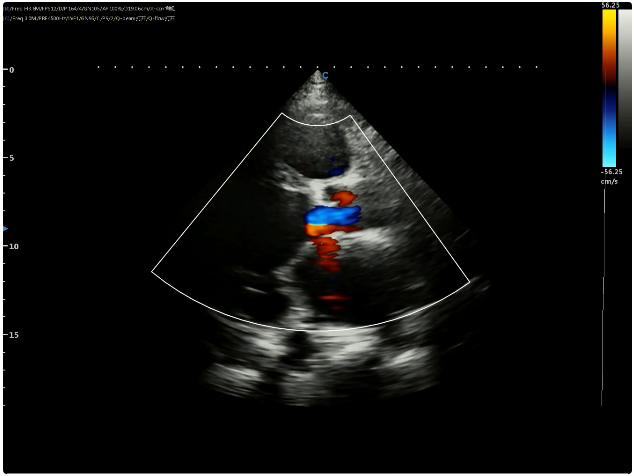

Measurements at Apical 4CH view in 2D Echo:

Left ventricular end diastolic diameter 73mm

Left ventricular end systolic diameter 67mm

Left atrium anterior posterior diameter 49mm

The upper and lower diameter of the left atrium was 67mm

Left and right atrium diameter 52mm

Right atrium 45mm

Left ventricle 66mm

Right ventricle 53mm

Widening of inferior vena cava.

Left ventricular wall motion is diffusely weakened, and the overall left ventricular function is severely reduced, EF=18%.

Mitral, tricuspid, and aortic valves have a small amount of regurgitation and the flow velocity of tricuspid regurgitation is Vmax=2.7m/s.